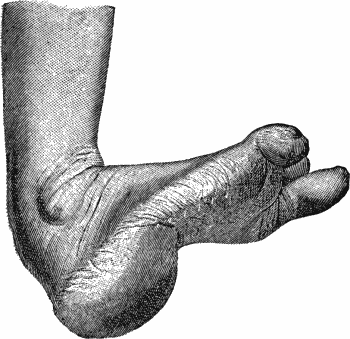

| 144. | Congenital Talipes Equino-varus in a Man | 277 |

| 142. | Bilateral Congenital Club-foot in an Infant | 274 |

| 143. | Radiogram of Bilateral Congenital Club-foot in an Infant | 275 |